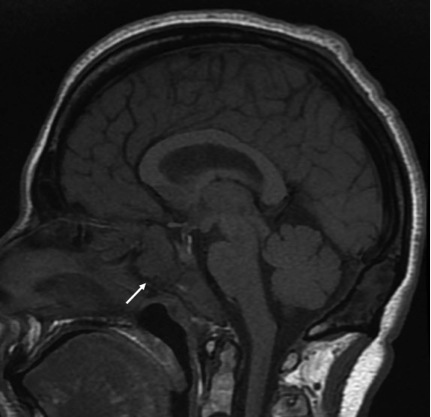

- На МРТ головного мозгавизуализирована микроаденома аденогипофиза размерами 7×6 мм (рис. 3) с инфраселлярным распространением, а также признаки диффузного утолщения левой верхнечелюстной и клиновидной пазух, клиновидной кости, латеральной стенки левой глазницы, базилярной части затылочной кости по типу фиброзной дисплазии (рис. 4).

Рис. 3. Пациентка М. МРТ головного мозга. Микроаденома гипофиза с пара-инфраселлярным распространением.

Описание. Турецкое седло деформировано, в правой части дно турецкого седла локально углублено. Структура аденогипофиза неоднородна за счет кистозно-солидного образования в его правой части, размерами 7×6 мм. Образование распространяется в пазуху основной кости.